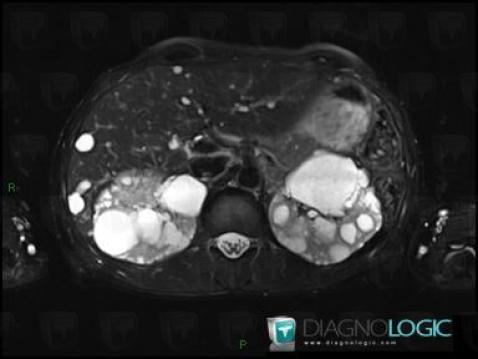

Polykystose rénale, Rein, IRM

Voici les informations spécifiques à l'image clé ci dessus:

- Diagnostic Polykystose rénale, Localisation(s) Rein, comportant les gammes Masse rénale en hypersignal T2, Masse rénale kystique, Maladie kystique rénale

- Diagnostic Polykystose rénale (lié à Kyste ), Localisation(s) Rein, comportant les gammes Masse rénale exophytique